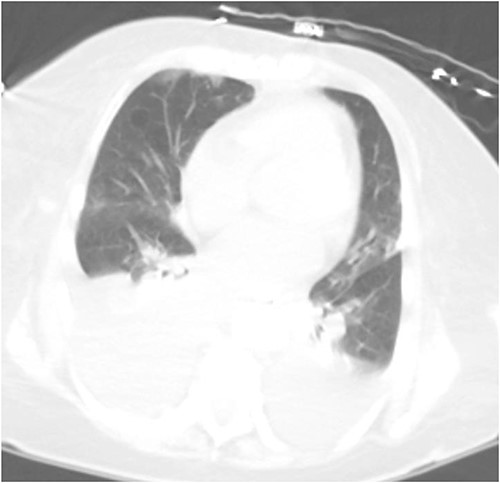

She was managed with bowel rest, parenteral nutrition, and octreotide. PCT output decreased but remained chylous throughout the hospitalization. Subsequent cholangiogram and PCT check revealed no fistulous connection to the thoracic cavity or lymphatic system (Fig. 5). Her hospitalization was further complicated by persistent distributive shock, adrenal insufficiency, and continued chyle leak. Though she was successfully extubated, her clinical status continued to decline. Per the wishes of the patient and family, she was transitioned to inpatient hospice and died shortly after.

PCT check using fluoroscopy showing the pigtail portion of the cholecystostomy tube within the gallbladder lumen as well as some leakage into the perihepatic space. No opacification of the pleural space.